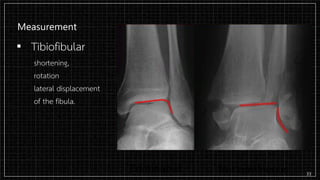

Measurement

▪ Tibiofibular

shortening,

rotation

lateral displacement

of the fibula.